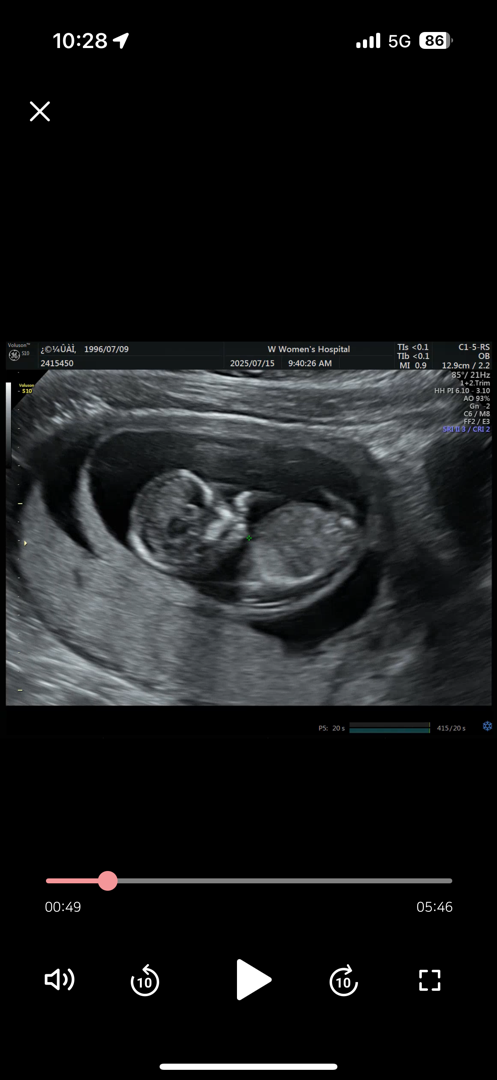

13주차 둥이 중 둘째인데 같이 봐주세요(사진은 한개씩 올료요)

둥이인데 둘째예요! 같이 봐주시면 감사합니다 ㅠㅠ 잘안보이지만...